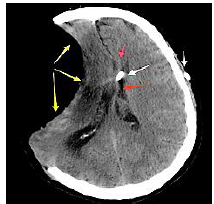

Paciente, sexo masculino, 65 anos, sofreu quadro de AVC isquêmico maligno em território de artéria cerebral média à direita há 1 ano, sendo necessária a realização de hemicraniectomia descompressiva extensa. Paciente evoluiu com recuperação parcial dos deficits neurológicos do AVC após muitas sessões de fisioterapia e terapia ocupacional. Estava aguardando cirurgia de cranioplastia, quando passou a apresentar quadro de sonolência excessiva, cefaleia e confusão mental. Realizou tomografia computadorizada de crânio que evidenciou o seguinte resultado:

Considerando o caso clínico hipotético, é correto afirmar que trata-se da síndrome: